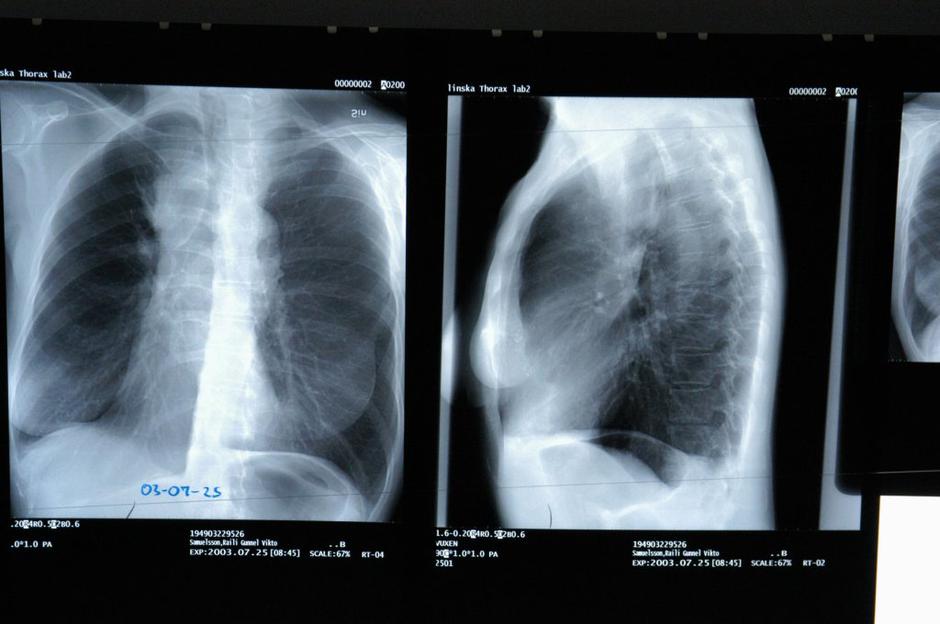

Pljučni rak

Pljučni rak je najpogostejši rak v svetovnem merilu in eden od petih najpogostejših rakov v Sloveniji, stiska bolnikov za pljučnim rakom pa je je danes v senci boja s Covid-19, ob letošnjem tradicionalno moškem mesecu novembru opozarjajo pri Društvu OnkoMan.

Pljučni rak | Avtor: Profimedia Profimedia

Rak pljuč je eden od rakov z najslabšo prognozo, saj je petletno preživetje bolnikov le 20-odsotno. Če je ta rak včasih veljal za neozdravljivega, danes odkritje v zgodnjih stadijih vendarle močno poveča verjetnost za preživetje. Onkologinja poziva, da ob simptomih čim prej obiščete zdravnika in pri tem vztrajate. Prvi obisk je po njenem izjemno pomemben. "Napredki v zdravljenju pljučnega raka so v zadnjem času na vseh področjih ogromni, raziskave pa potekajo kljub epidemiji," je dodala.